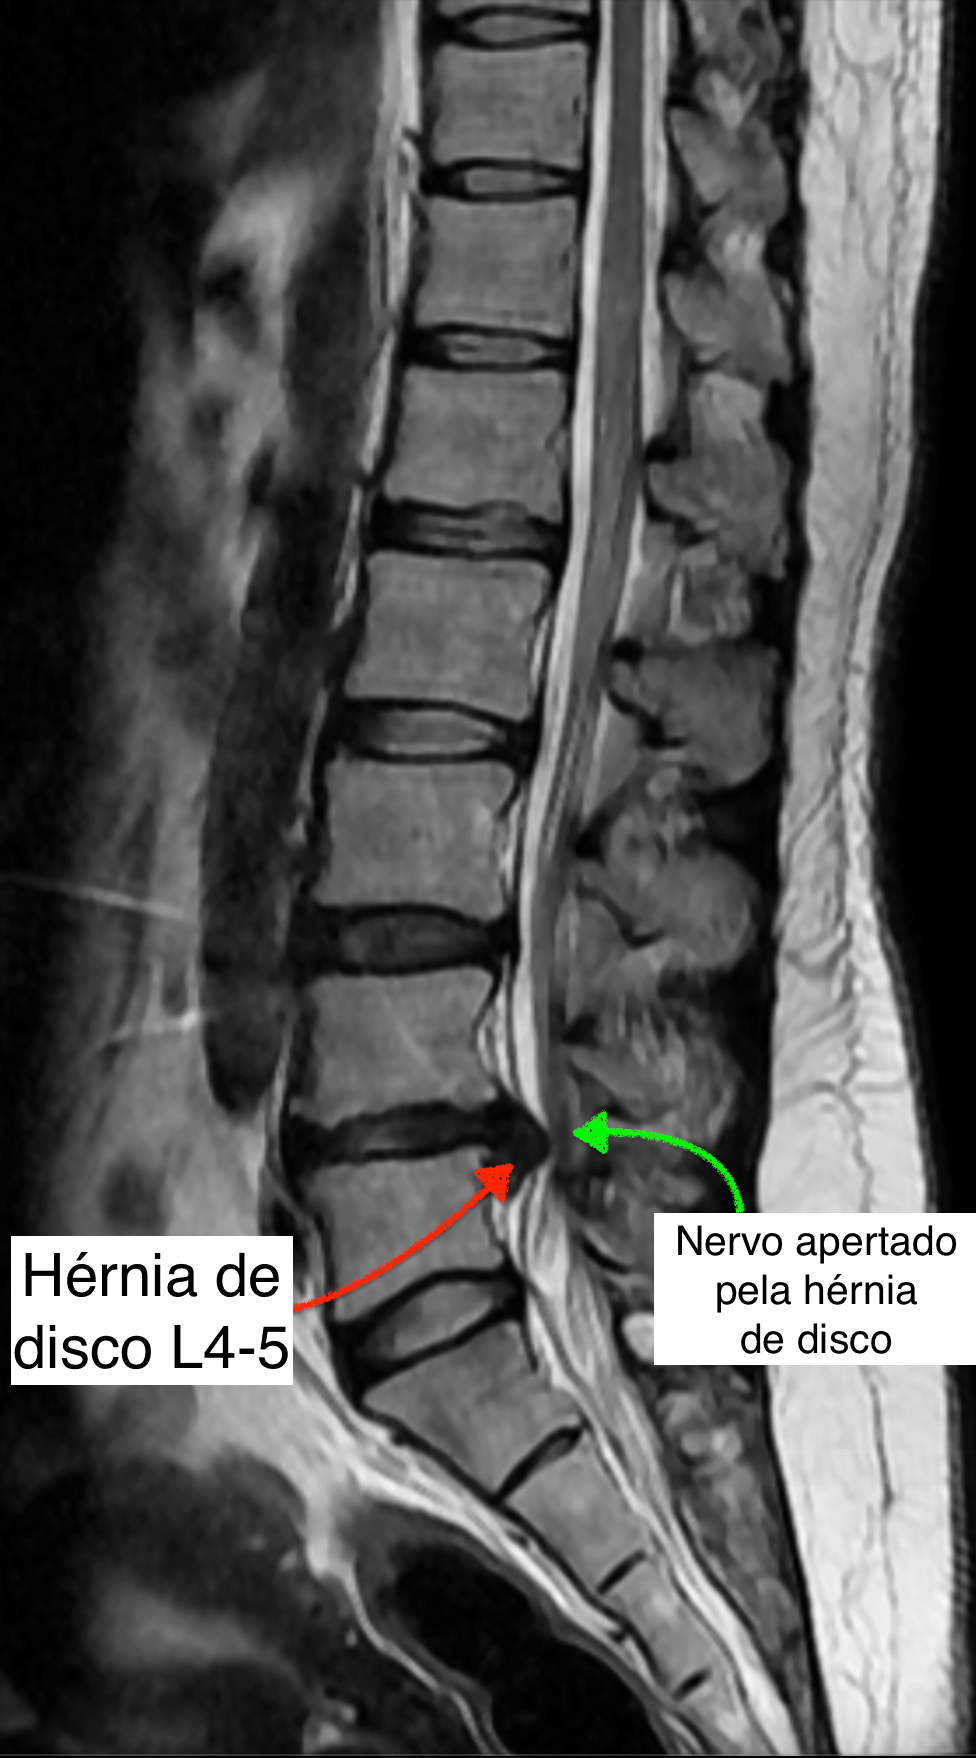

O principal exame de imagem é a ressonância magnética da coluna lombar, que mostra com detalhes a presença da hérnia, sua localização e se há compressão de raízes nervosas.

Entre as vértebras da coluna existe uma estrutura chamada disco intervertebral, que funciona como um amortecedor, permitindo mobilidade e absorvendo impactos. Esse disco é formado por um centro gelatinoso (núcleo pulposo) e uma parte mais resistente ao redor (ânulo fibroso).

Com o tempo, ou após sobrecargas repetitivas, o disco pode se desgastar e seu conteúdo interno pode se projetar para fora, formando o que chamamos de hérnia de disco. Quando isso acontece na região lombar (parte baixa das costas), chamamos de hérnia de disco lombar.

Essa hérnia pode comprimir estruturas nervosas próximas, como as raízes do nervo ciático, causando dor e outros sintomas.